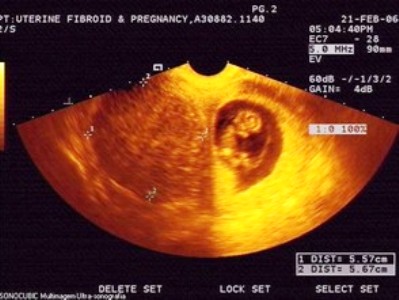

Может ли миома быть ошибочно принята за беременность? Да, это возможно, особенно если опухоль достаточно велика и не проводилось ультразвуковое исследование.

Если зачатие все же произошло, необходимо внимательно следить за состоянием беременной женщины с помощью УЗИ. Она должна чаще посещать врача, который будет контролировать рост миомы и ее влияние на развитие плода.

Иногда бывает так, что у женщины до наступления беременности не было никаких медицинских проблем, и вдруг, во время планового УЗИ, ей ставят диагноз миома.